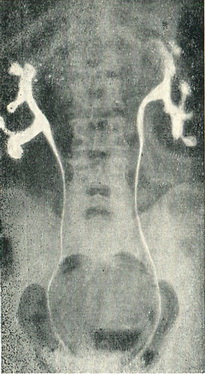

Діагноз грунтується на прощупываемых з обох боків збільшених, щільних, горбистих нирок, явищах ниркової недостатності, гематурії, гіпертонії. Важливу діагностичну допомогу надає ретроградна пієлографія, яка дає картину надмірної гіллястості, подовження, витягнутості чашок з обох сторін (рис. 58).

Рис. 58. Полікістоз нирок. Двостороння ретроградна пієлограма.